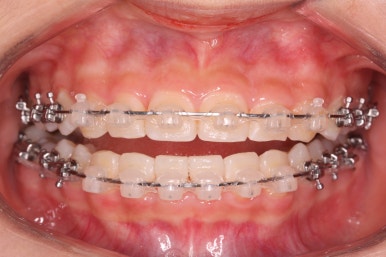

윗니에도 이제 장치를 모두 붙였습니다. 아래쪽은 어느 정도 가지런해지고 나면 부족한 자리를 만들어주기 시작합니다.

부산치아교정잘하는곳 키다리아저씨치과에서 이번 환자분에 사용한 장치는 데이몬 클리어라고 하는 세라믹 자가결찰 장치입니다. 세라믹 자가결찰 장치 중에서 철사를 잡아주는 CAP 부위까지 세라믹으로 되어있어 가장 심미적인 장치라고 볼 수 있습니다.

장치 부착 후 얼굴 모습 보여드리겠습니다.

특히 웃을 때 철사 이외에는 장치가 크게 눈에 띄지 않아서 심미성을 원하시는 분들이 많이 선택을 하는 장치입니다.

부산치아교정잘하는곳 키다리아저씨치과에서는 치아가 올라오자마자 장치를 부착하여 가지런하게 해줍니다. 이제 어느 정도 큰 그림은 그려졌다고 보시면 되겠습니다.

어느 정도 큰 그림이 그려졌으면 중앙선이라든지 치아의 디테일한 면을 더 수정하고 마무리하게 되겠습니다.

치료 종료 후의 모습입니다.

치아들이 가지런하게 되었고, 나오지 못하던 치아도 잘 나와서 가지런해졌습니다.

해당 부위 앞뒤로 쓰러져 있던 치아들도 축이 바로 잡혔고, 자연스레 위-아래 치아의 중앙선도 맞아졌습니다.